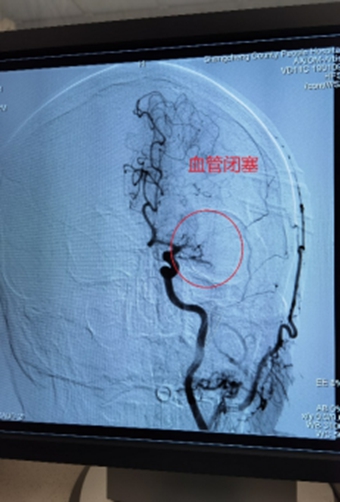

在商城县人民医院卒中中心几乎每天都上演着这样惊心动魄的生死救护。无独有偶,近2周来我院已独立完成4例急诊机械取栓。

1、左侧颈内动脉末端闭塞,急诊导管抽栓+支架拉栓1例;

2、基底动脉栓塞,急诊导管抽栓+动脉溶栓1例;

3、左侧大脑中动脉M1起始处闭塞,急诊导管抽栓1例;